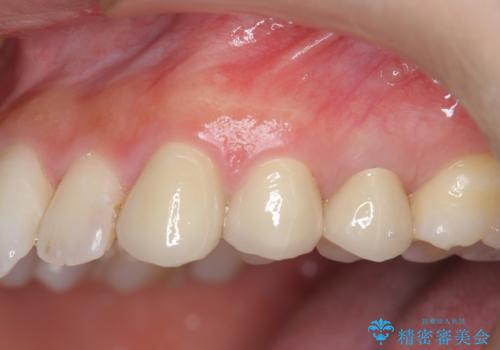

小矯正を行い深い虫歯を改善した後は、小手術を行うことで歯ぐき・周囲歯槽骨の状態を整えることでより安定した歯周環境を得ることができます。